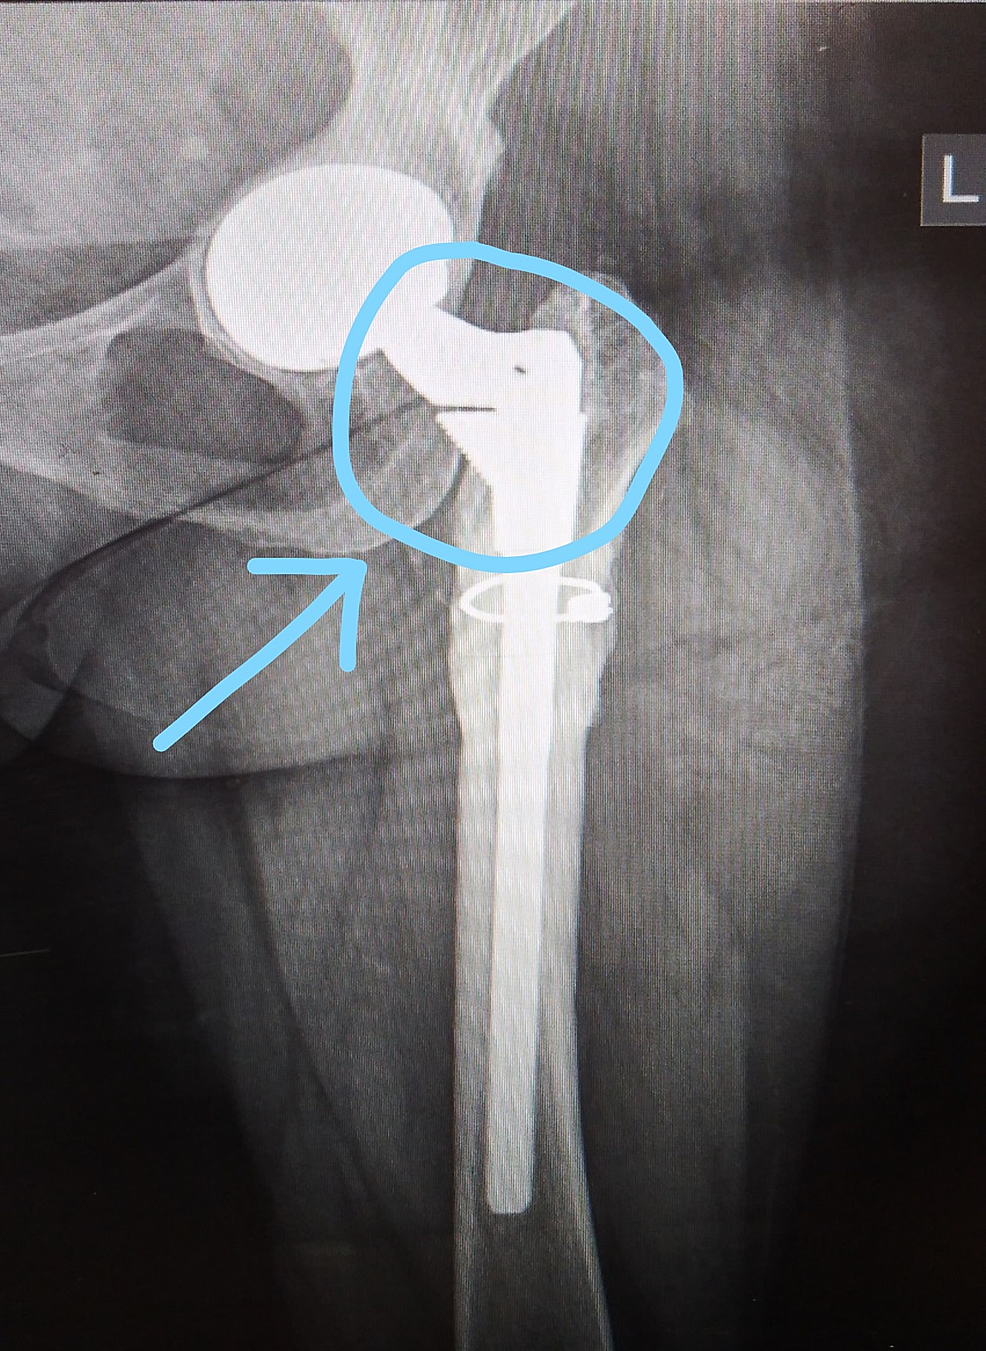

On a lighter note, the implant which is shown in the above-mentioned patient is a modular implant (S-ROM modular hip system) system, if you look at it closely, it looks like a happy elephant. So we call it a “Happy Elephant sign” (Figure 3).

We recommended a hip replacement and discussed the potential benefits and risk factors. It was explained to the patient that in dealing with the developmental dislocation we would have to recreate normal hip mechanics which requires positioning of the acetabular component in hemispherical acetabular cavity at the centre of rotation. It would also entail placing a femoral component at a much lower level within a femoral canal which was abnormally narrow. She underwent the left hip replacement which was surgically challenging. A special hip implant was used for the hip replacement. It was a modular implant typically used for difficult cases where there is anatomical distortion. The surgery was completed without any complications. We were able to correct the leg length discrepency by 4cm. Following surgery the patient underwent physical therapy and is now independently mobile without the use of external support and has no functional difficulties in day to day activities, (Figures 1-2).